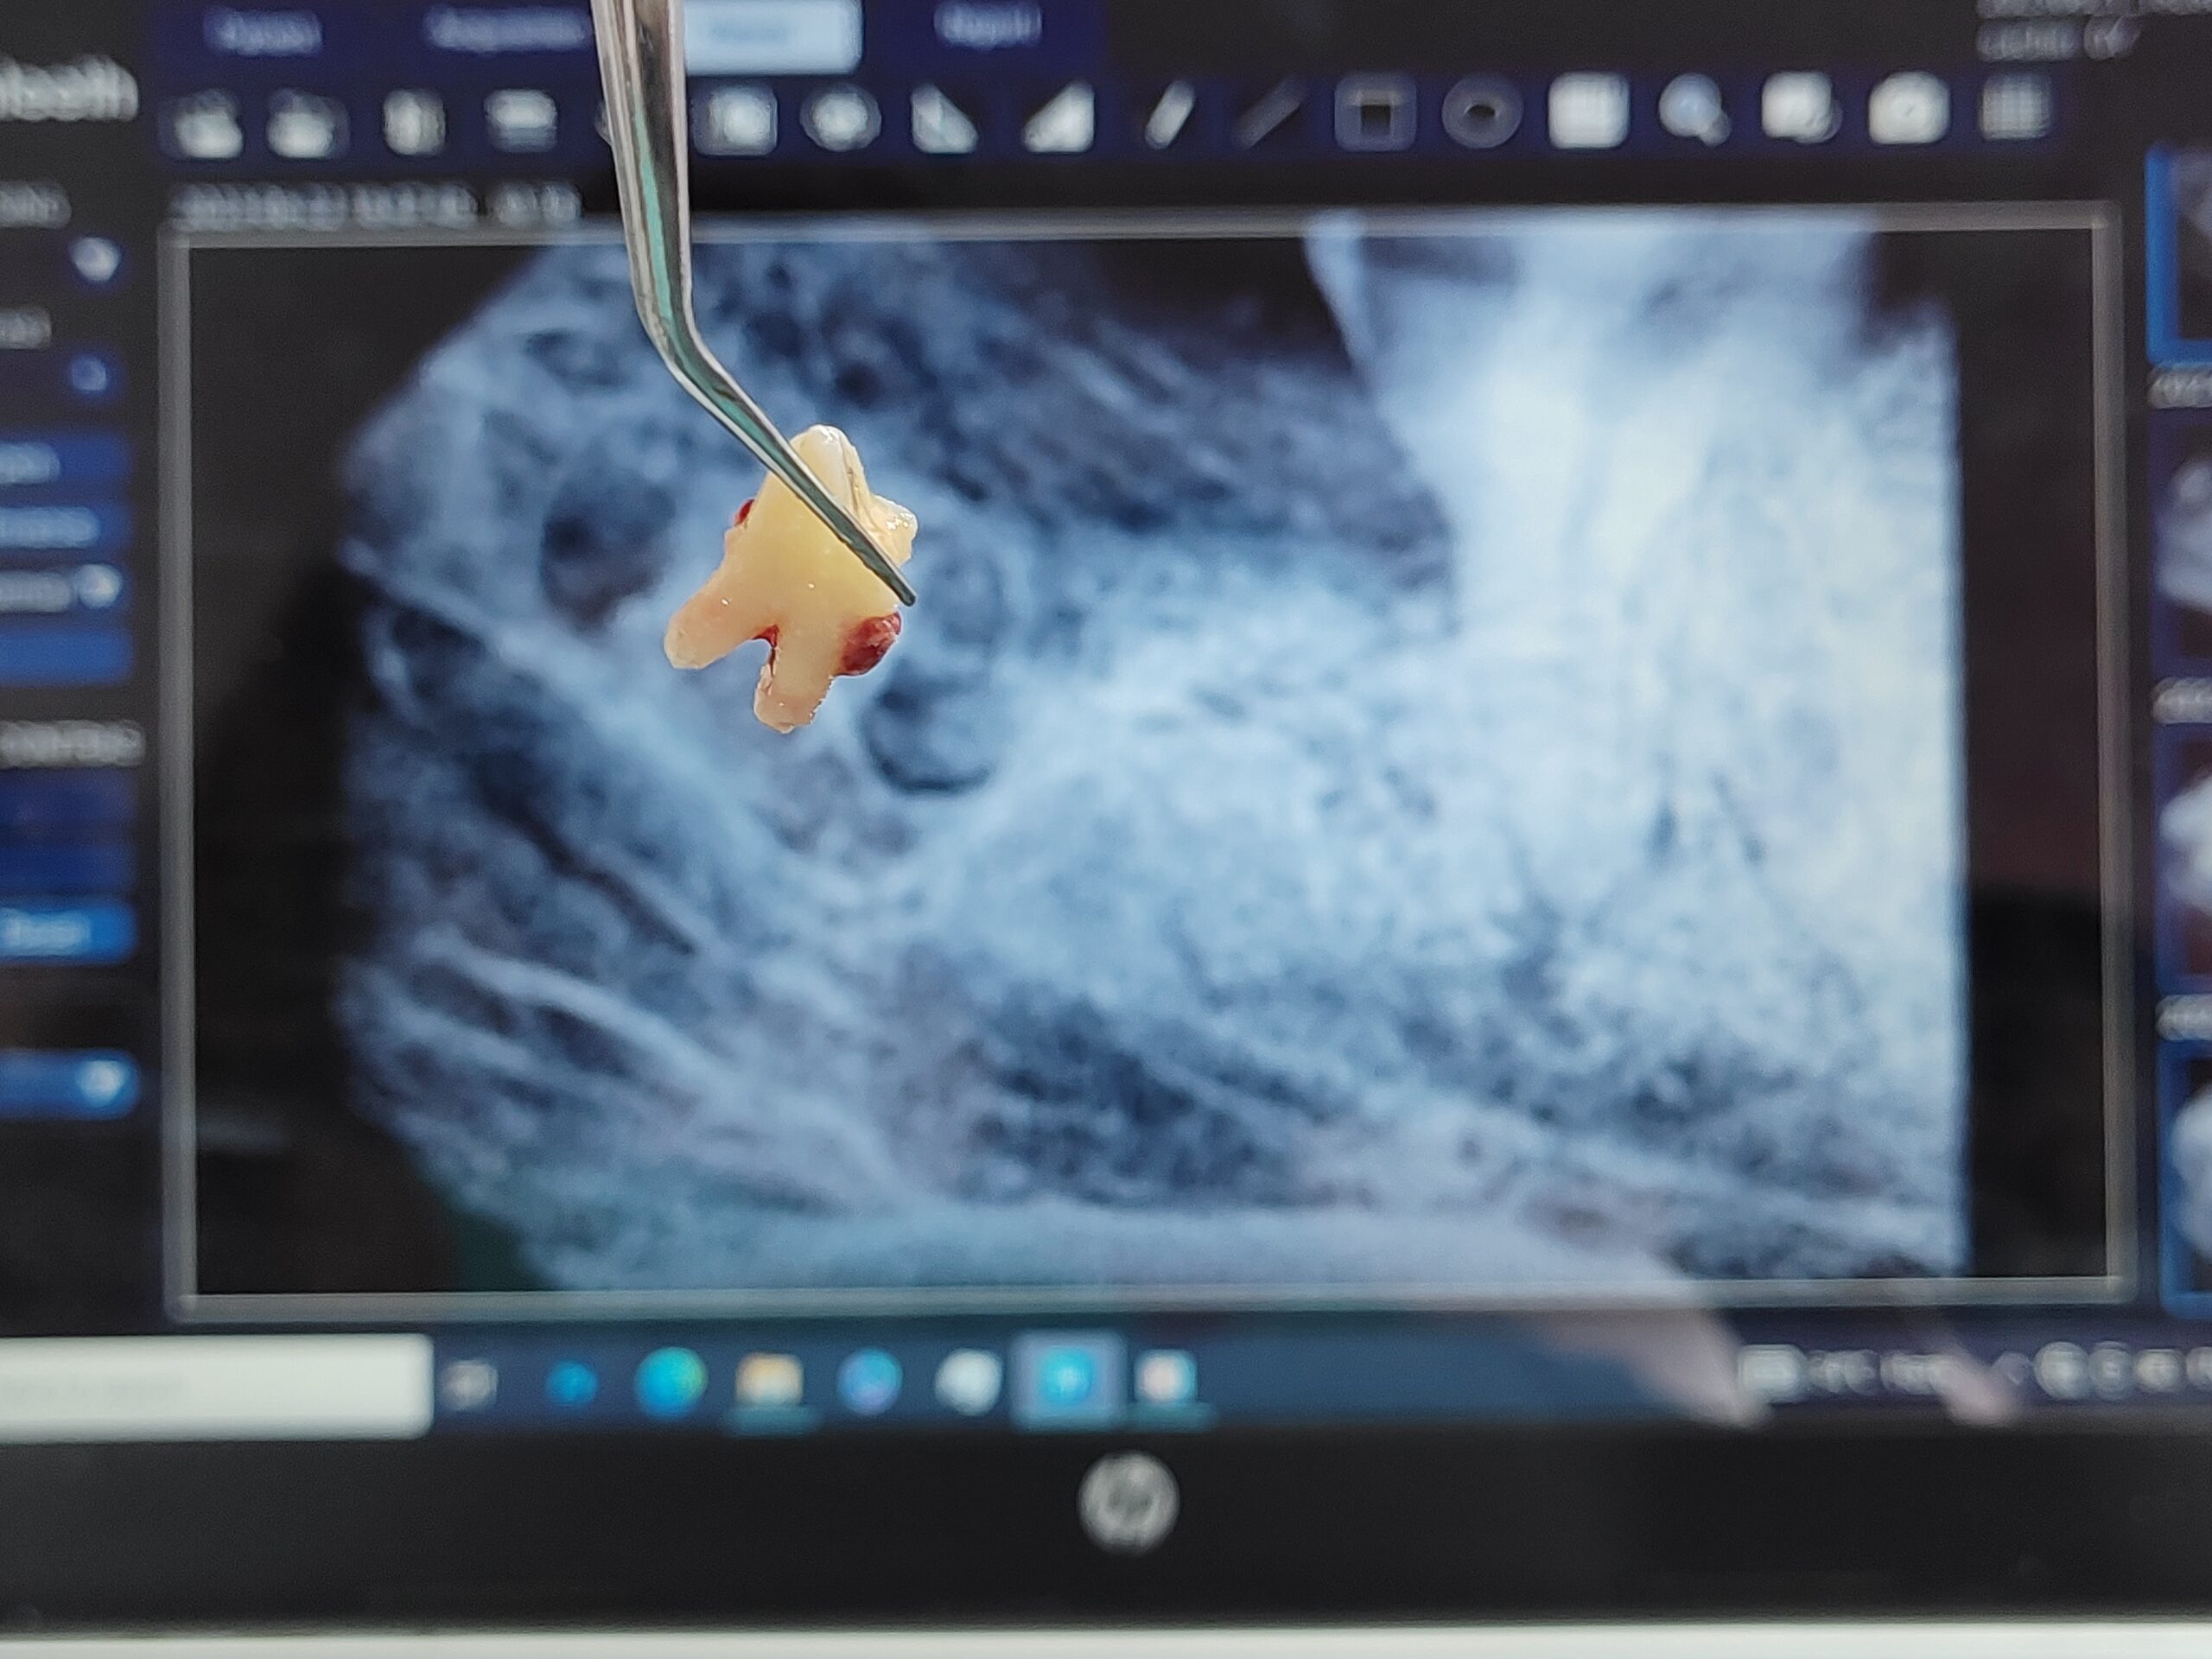

Single Sitting Root Canal Treatment (RCT)

specialize in single-sitting, painless root canal treatments using advanced rotary systems and magnification for accuracy.

Wisdom Tooth Removal

Safe and gentle extraction of impacted or painful wisdom teeth by a skilled oral surgeon.